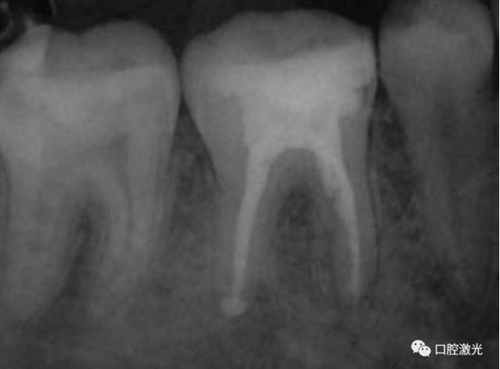

46治療前X光片

半導(dǎo)體激光治療中

6個月后治療效果